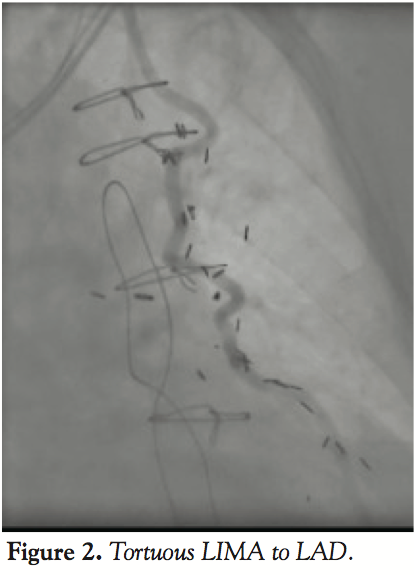

After a review of the angiographic images, we determined that the lesion in the LAD could not be visualized during native left coronary angiography (Figure 1). PCI of the LAD could not be performed through the LIMA due to its severe tortuosity (Figures 2 and 3).